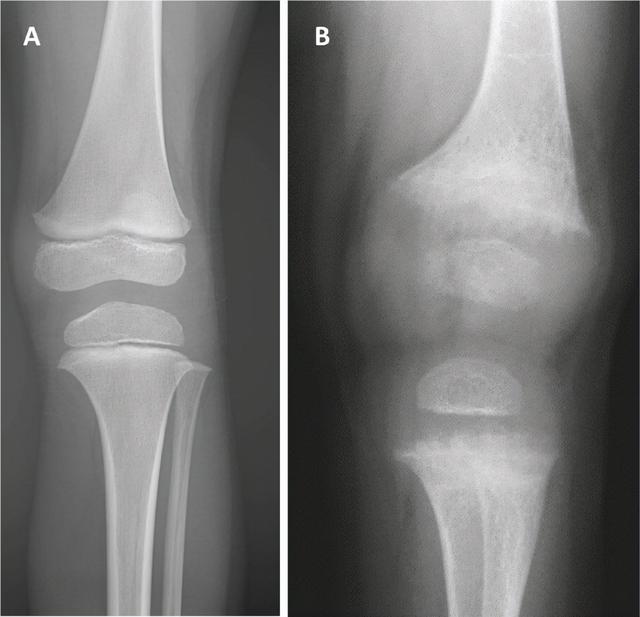

布雷特错了。x光显示出一个大问题。在x光片中,正常发育的骨骼是明亮透明的。小女孩是浅灰色半透明的。在大腿和小腿的每根长骨的末端,都有一个叫生长板的区域,在x光片上应该会显示出清晰的线条,但是小女孩的x光片是模糊的。这就像没有正确对焦就拍照一样。

古川马上就认出了这个片子上的问题,佝偻病!这是由于缺乏一种或多种使骨骼强壮的必需维生素或矿物质。——通常缺乏维生素D和钙,也可能缺乏磷酸盐,但并不常见。维生素D可以使身体吸收钙和磷酸盐,这是强壮骨骼的两个基本成分。几年前,饮食中维生素D缺乏是佝偻病最常见的原因,现在一些贫困地区依然如此。但在大多数国家很少见,因为很多食物都富含维生素D,所以现在佝偻病主要见于一些母乳喂养6个月以上,没有补充维生素D的婴儿。虽然孩子很小,但似乎并不缺乏营养。她妈妈还说她胃口很好,经常吃富含维生素D和钙的食物。